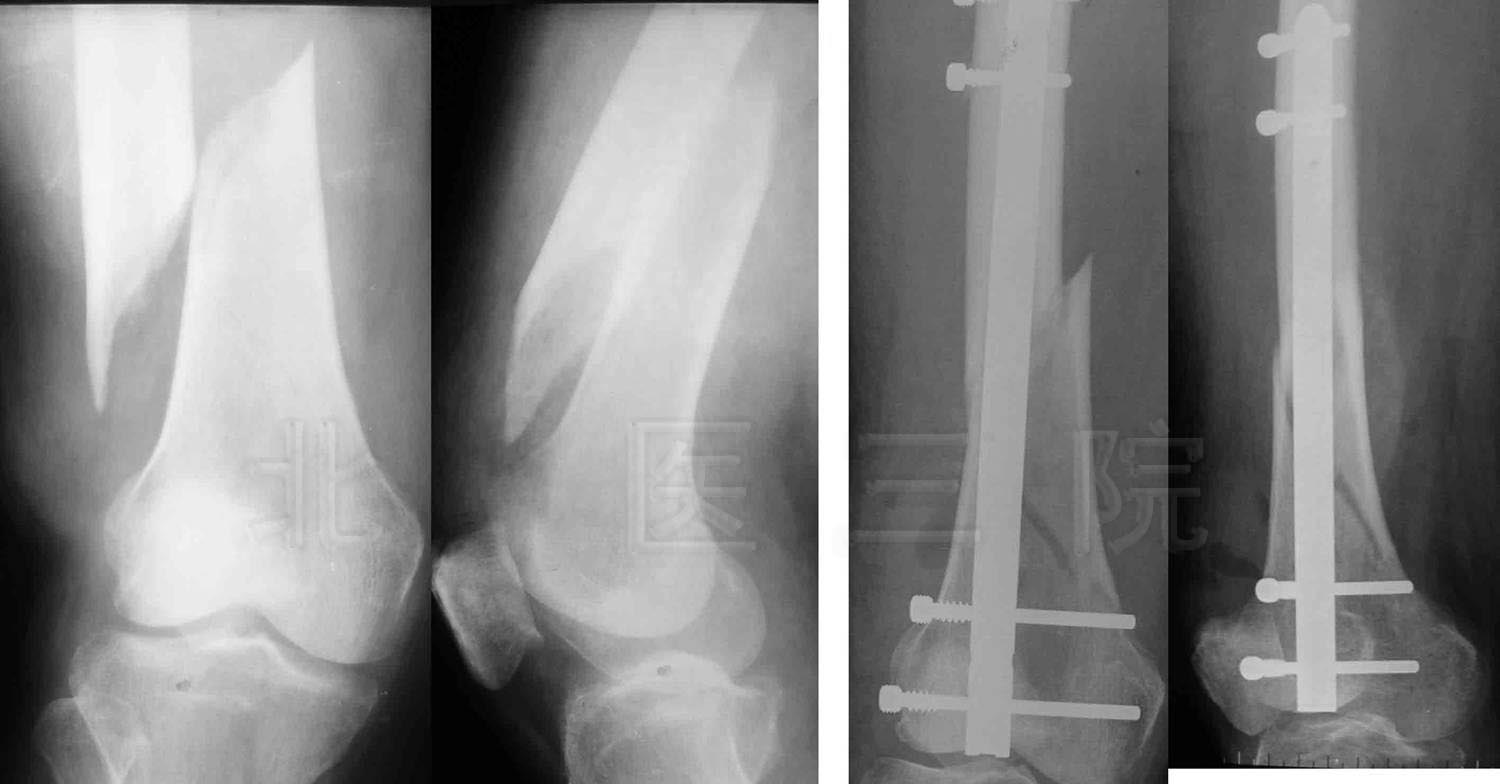

1.女,65岁,肱骨髁间粉碎性骨折,术后肘关节功能大部分恢复

2.前臂双骨折,交锁髓内钉固定

3.桡骨末端掌侧Barton骨折

4.男,35岁,车祸致多发创伤

1)股骨上端骨折

2)胫腓骨下端粉碎性骨折

3)L1、L2骨折

5.女,66岁,外伤致股骨下端骨折,行股骨逆行交锁髓内

钉固定术

6.女,43岁,车祸致胫骨平台骨折

7.男,49岁,胫腓骨骨折,径胫骨髓内钉固定+腓骨钢板固定

8.男,44岁,高处坠落伤致左髋臼、骨盆骨折

9.男,55岁,高处坠落伤致跟骨骨折